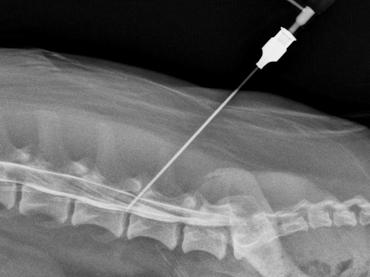

Диагностика межреберной невралгии

При обращении в медицинское учреждение, врач должен осмотреть больного, а также расспросить о мучающем вопросе.

После выдвижения предположительного диагноза требуется пройти ряд обследований:

Новейшая диагностика — электроспондилография. Используется для выявления общего состояния позвоночника, а также влияние на него проводимых медицинских процедур.